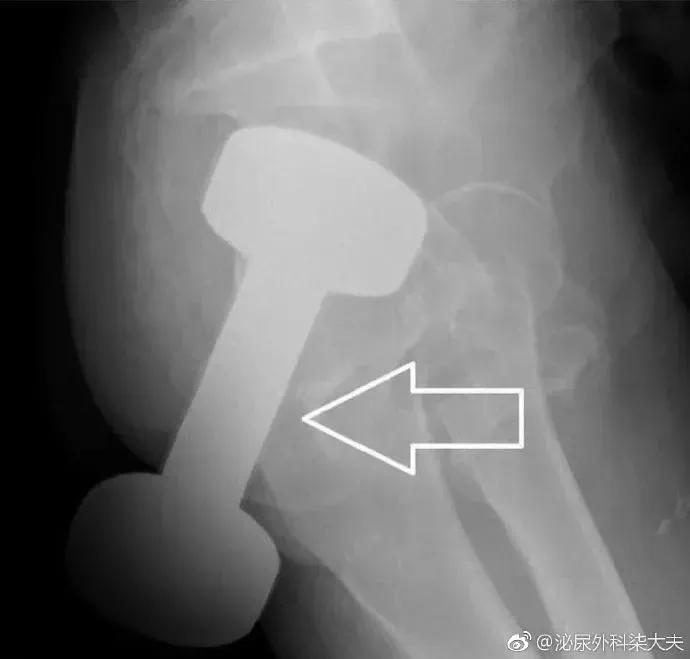

医生会通过一系列检查如直肠指诊、X线来确定体内的异物是什么,在什么位置,这一点非常关键,因为只有搞清楚里面的真实情况,医生才能找到合适的方法把异物取出。

急诊来了个患者,直肠异物,平片显示是个灯泡,灯泡当然是要取出来的。但有两个要求:第一,不能把灯泡弄碎,这样可能会损伤直肠;第二,尽量不做手术,手术创伤大,如果做手术,可能要做造口。满足两个条件的前提下大家有什么好方法把灯泡完整取出?